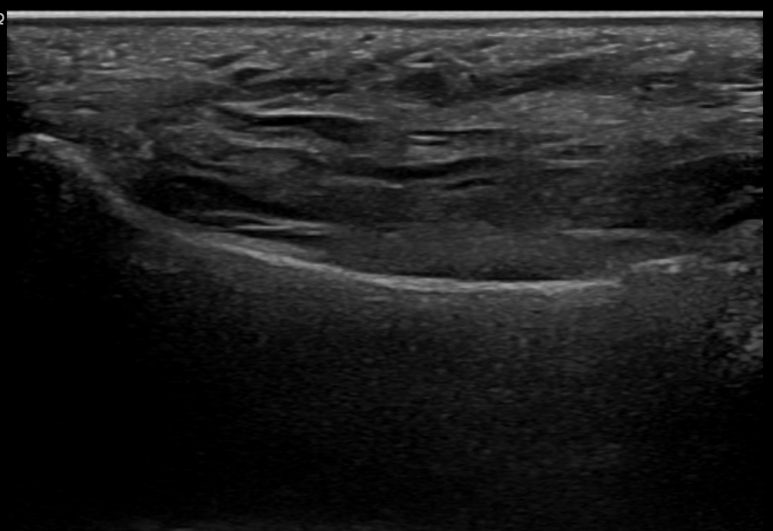

한의학적으로 어혈/담음증에 해당하여 경혈초음파를 시행했습니다.** > 경혈 초음파 등 뿐만 아니라 발바닥쪽 통증도 호소하셔서 족소음신경 용천혈(溶泉穴) 주변을 초음파로 관찰한 영상입니다.**

용천혈 주변 좌측 / 우측

좌측의 정상 뼈 모습**은 표준 경혈 초음파 영상과 동일한데요.

우측 용천혈의 아래쪽에서 연속되어야 할 뼈가 끊어져보입니다.